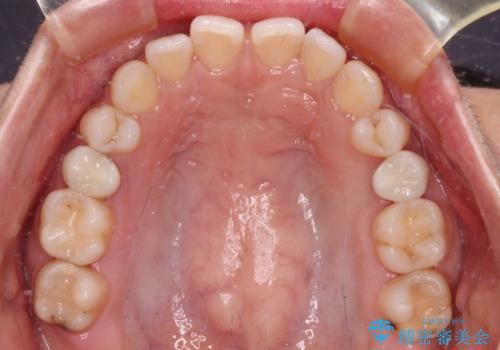

- 奥歯が割れてしまい、抜歯が必要となった患者様です。

以前にも歯が割れてインプラント治療を行いましたが、抜歯してからインプラント埋入→仮歯装着までに半年以上を要し、その間に残された歯への負担が大きくなり、左右反対側のセラミッククラウンが破折したことがありました。